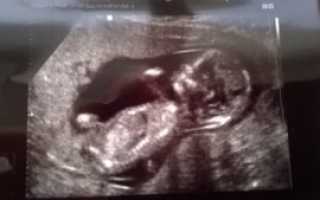

Симптомы и диагностика: Женщины с гипертонусом могут испытывать дискомфорт, боли внизу живота или ощущение напряжения в области матки. Важно, чтобы будущие мамы обращали внимание на эти симптомы и сообщали о них врачу, так как это может потребовать дополнительного наблюдения и, возможно, лечения.